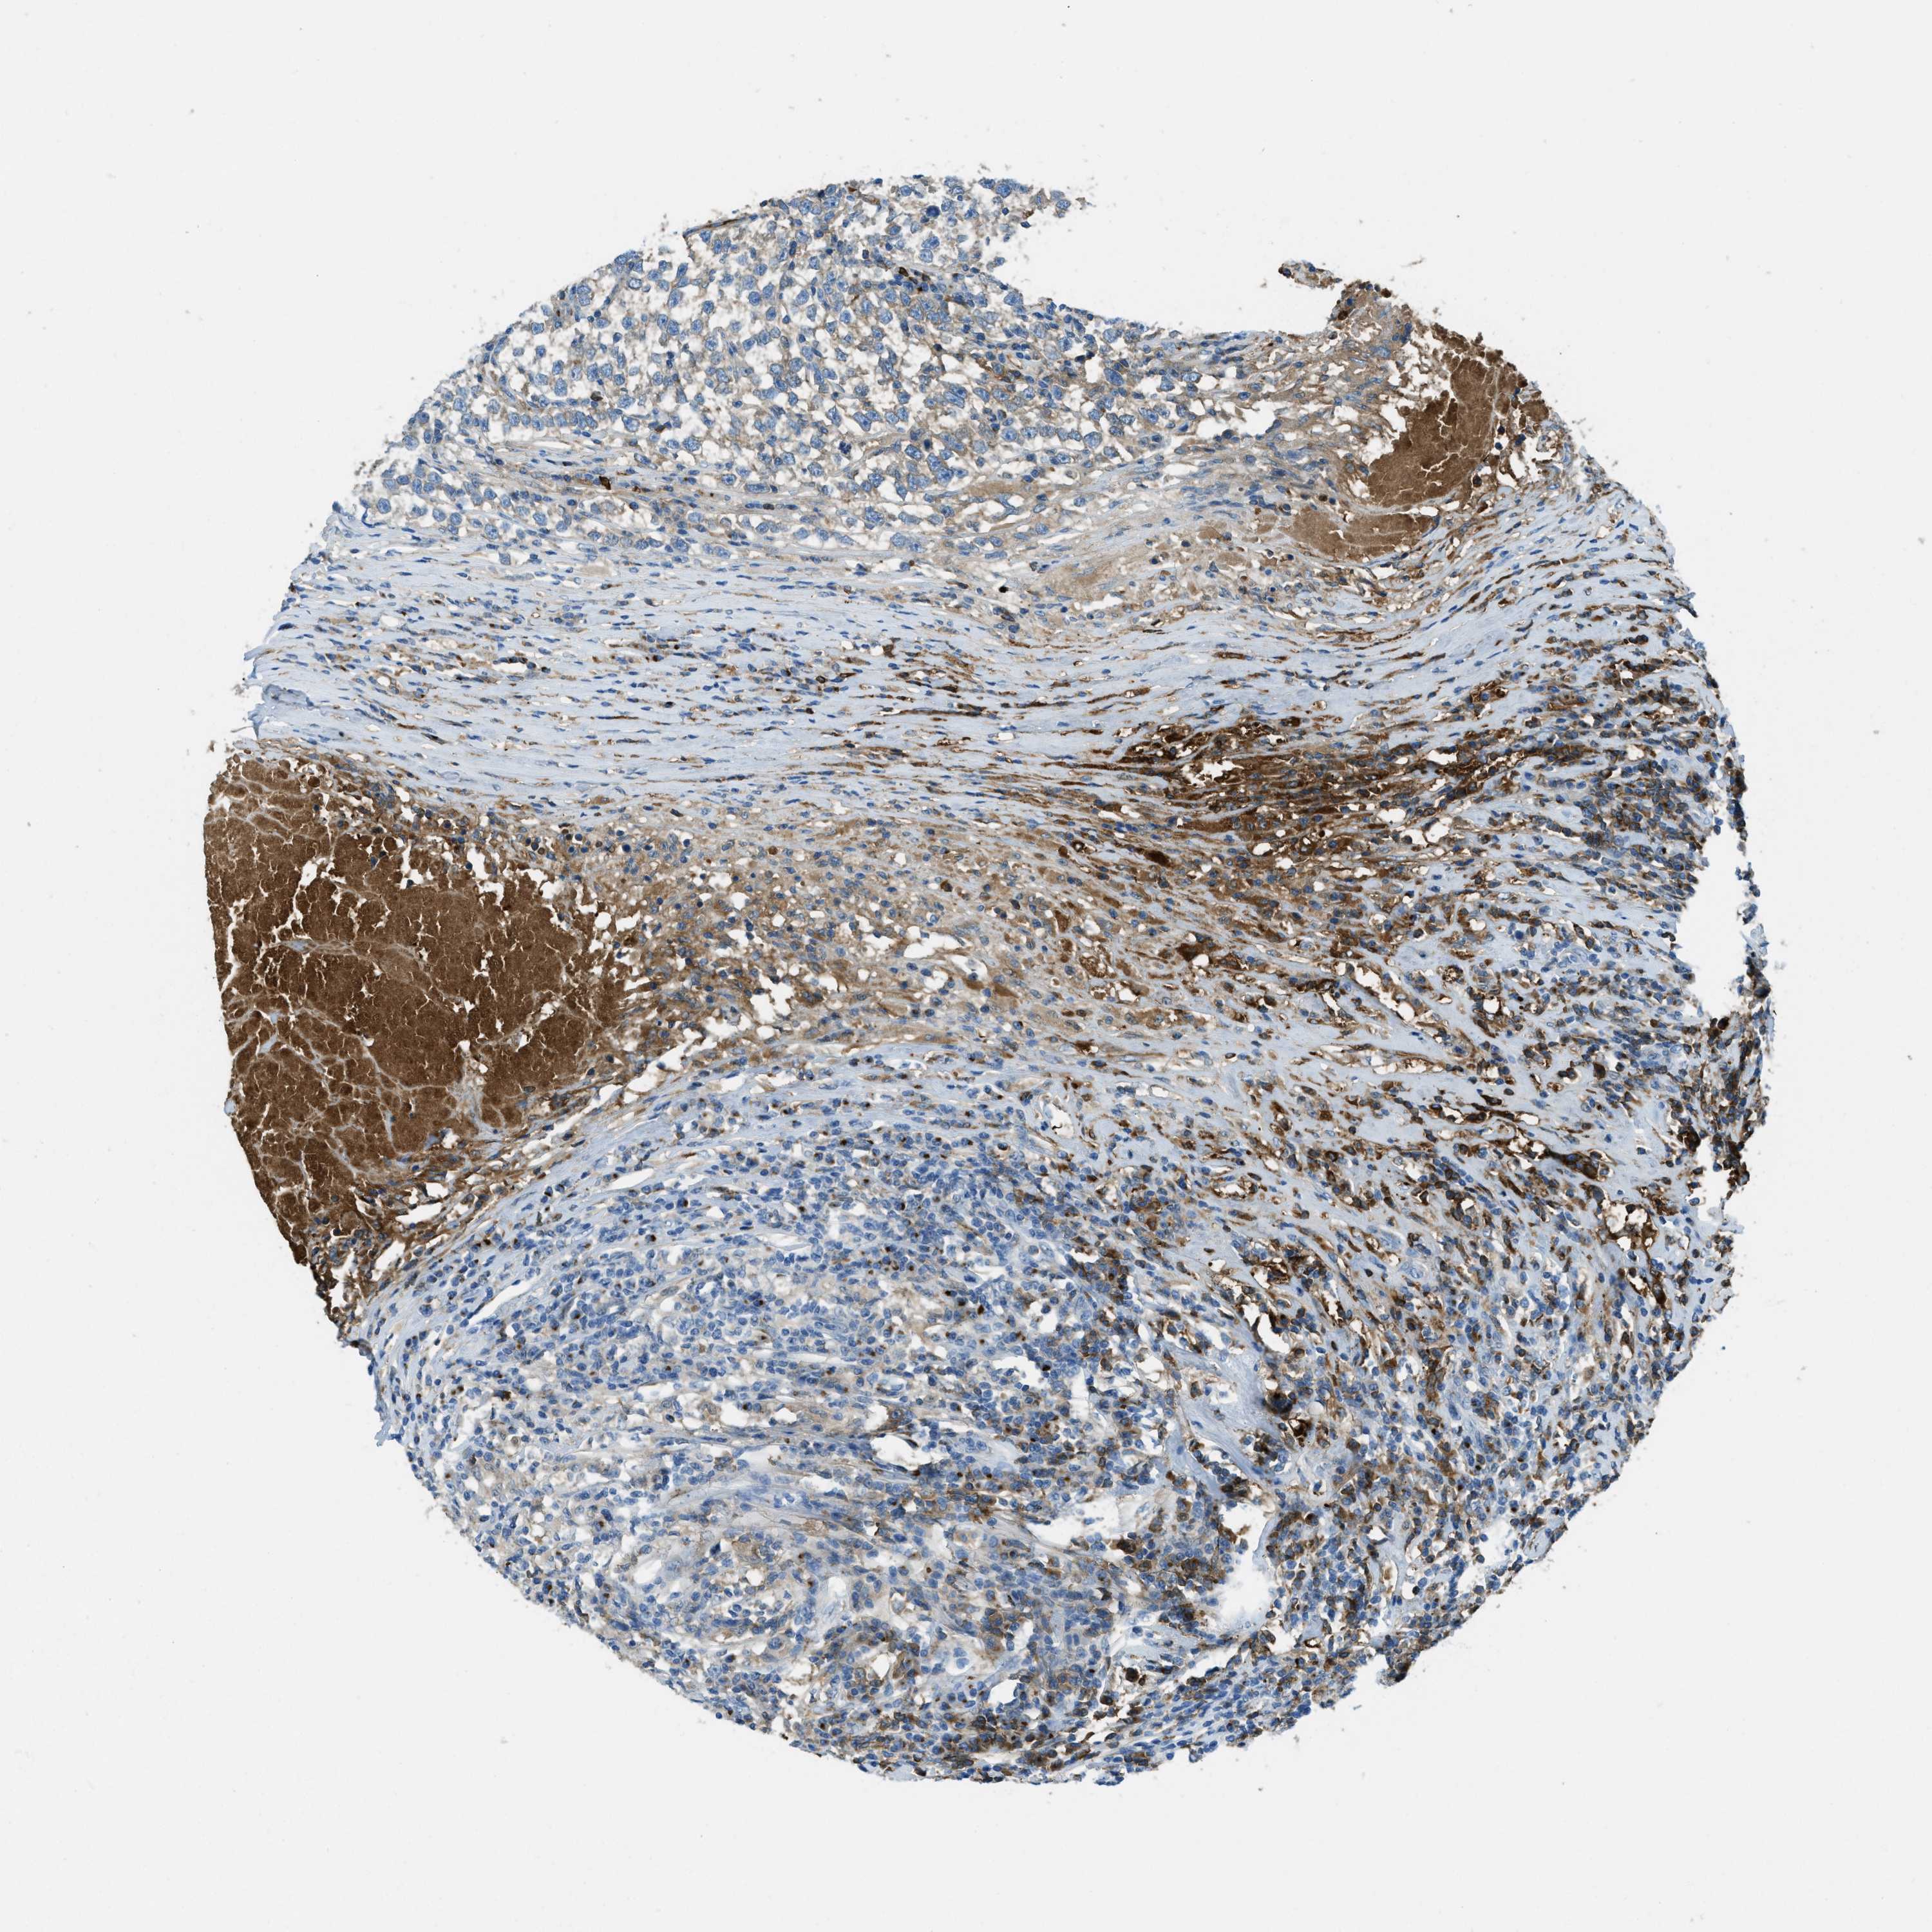

TESTIS CANCER - Protein expressioni

A mouse-over function shows sample information and annotation data. Click on an image to view it in a full screen mode. Samples can be filtered based on level of antibody staining by selecting one or several of the following categories: high, medium, low and not detected. The assay and annotation is described here.

Note that samples used for immunohistochemistry by the Human Protein Atlas do not correspond to samples in the TCGA dataset.

Antibody stainingi

Antibody staining in the annotated cell types in the current human tissue is reported as not detected, low, medium, or high, based on conventional immunohistochemistry profiling in selected tissues. This score is based on the combination of the staining intensity and fraction of stained cells.

Each image is clickable and will lead to virtual microscopy that enables deeper exploration of all samples and also displays staining intensity scores, fraction scores and subcellular localization as well as patient and tissue information for each sample.

Antibody HPA017750

Staining

High

Medium

Low

Not detected

Intensity

Strong

Moderate

Weak

Negative

Quantity

>75%

75%-25%

<25%

None

Location

Nuclear

Cytoplasmic/membranous

Cytoplasmic/membranous,nuclear

Carcinoma, Embryonal, NOS

Seminoma, NOS